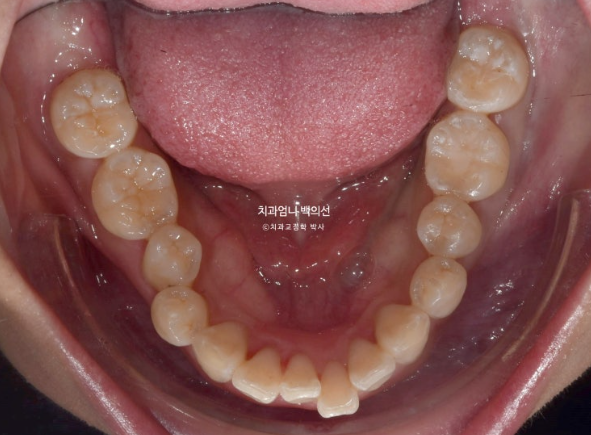

돌출입 교정을 위해 내원하신 분입니다.

정면을 보시면 윗니가 아랫니를 많이 덮고 있습니다.

아랫니가 거의 보이지 않습니다.

이런 부정교합을 과개교합 이라고 합니다.

윗니도 많이 뻗쳐 있습니다.

배열도 좋지 않아서 발치교정 권유드렸습니다.

위 작은어금니 2개 발치 아래는 매복사랑니 발치 후 작은 어금니 발치 없이 미니스크류를 심고 후방이동 하는 계획입니다.

교정장치는 인비절라인이며 23년 3월에 장치를 끼기 시작했습니다.